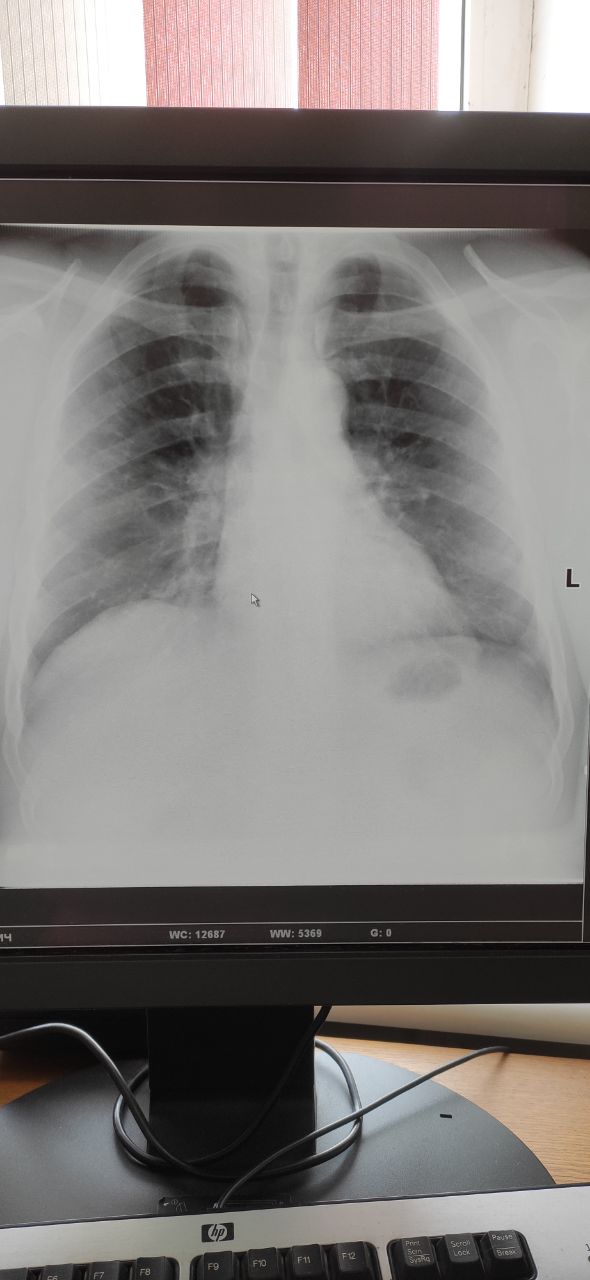

Женщина, 49 лет, жалобы кашель, температура 37.4. здесь двухсторонняя или я уже придираюсь

Лично мне с 2 сторон не нравится

После перенесенога эксудативной плеврит

Ковид

Да двухсторонняя пневмония, но по стандарту диагностики больных с SARS COV2 ,надо КТ ей

Симптом матового стекла , если я не ошибаюсь